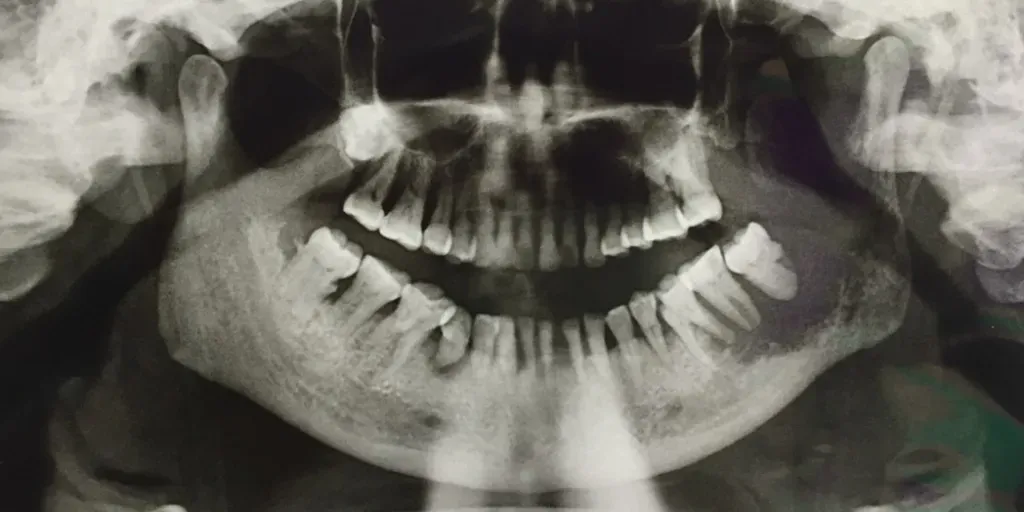

When your dentist performs a screening for oral cancer, they will look in your mouth for the following:

- White or red patches

- Hard spots or lumps in your mouth or on your gums

- Pain or a numb feeling when you bite

- Spots or sores that are not healing

If your dentist asks you any questions during the screening, always answer as honestly as you can. If a suspicious spot is found in your mouth, a tissue sample will be sent to another lab to test for the presence of cancerous cells.